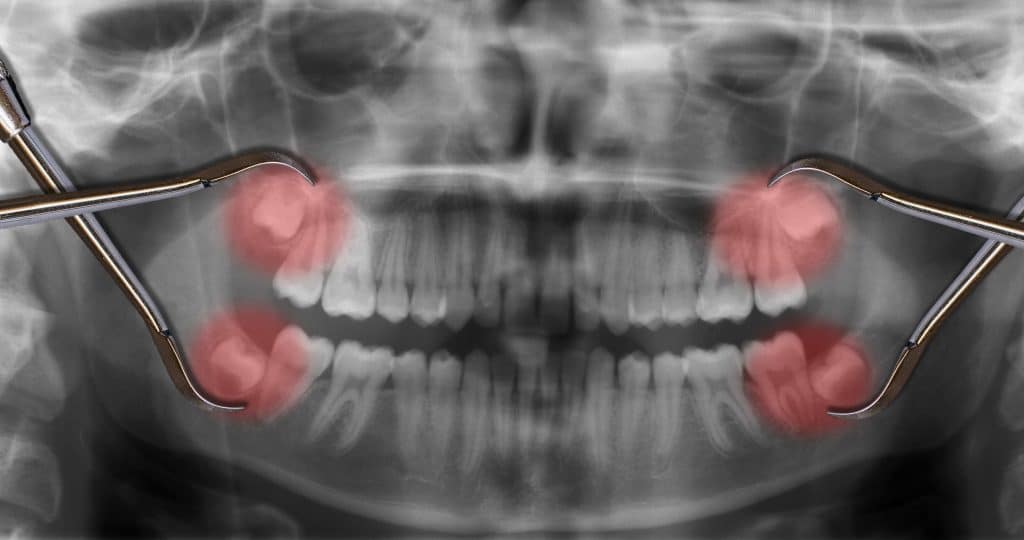

Recovering from wisdom teeth removal typically takes a few days. Following all post-surgery instructions is important for a smooth recovery, especially within the first 24 to 48 hours. Knowing what to eat can help you heal properly and stay comfortable. Here is a helpful guide to the best foods to eat after a wisdom tooth removal in Fort Collins, CO, along with other tips to ensure a safe and swift recovery process.

You may not feel like eating right after the procedure, particularly if your wisdom teeth were impacted. Your mouth, jaw, and cheeks will likely be tender and swollen, and you will have gauze in place. However, eating is necessary to fuel a healthy recovery.